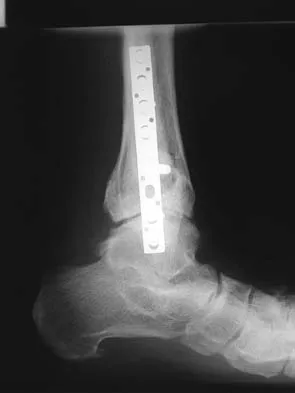

A 38-year-old man underwent a transtibial amputation for chronic posttraumatic foot and ankle pain and chronic calcaneal osteomyelitis. Postoperative radiographs are seen in Figures 41a and 41b. What is the proposed purpose of the surgical modification seen in the radiographs?

The Ertl modification of a below-knee amputation has been proposed to create a more stable "platform" to aid in transferring the load of weight bearing between the residual limb and the prosthetic socket. It is felt that a stable platform allows total contact loading over an enlarged stable surface area. Early studies have suggested that this modification may enhance the patient's perceived functional outcome. Pinzur MS, Pinto MA, Saltzman M, et al: Health-related quality of life in patients with transtibial amputation and reconstruction with bone bridging of the distal tibia and fibula. Foot Ankle Int 2006;27:907-912.